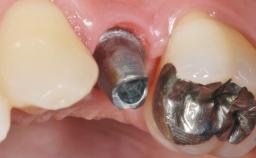

Early Placement of an Implant in a Maxillary Right Central Incisor Site

| Abutment Type | Customized |

| Prosthesis Type | FDP |